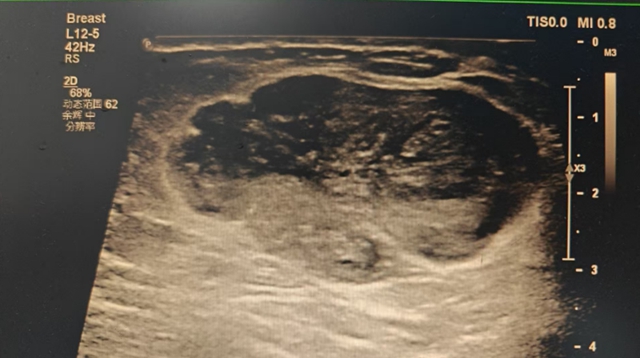

女子左胸出現(xiàn)腫塊,一查竟是瘤!醫(yī)生:日常乳房自檢很重要

當54歲的楊女士發(fā)現(xiàn)左側(cè)乳房長了硬塊時,她怎么也沒想到,這個看似普通的腫塊背后,竟是腫瘤警報?! 〗?,楊女士偶然發(fā)現(xiàn)她的左側(cè)乳房有一個“雞蛋”大小的硬塊,但是摸著不痛,也沒有其他不適的感覺?! ¢L結(jié)節(jié)了?  隨后幾天,楊女士一直在觀察腫...